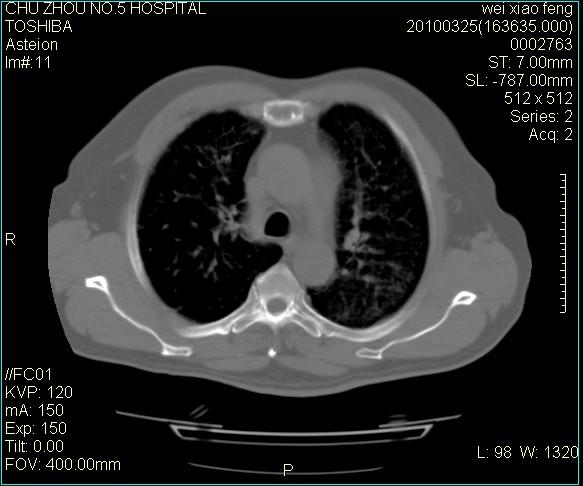

男,60岁,反复咳、痰、喘3月,加重3天。

双肺间质性改变。

考虑双肺血型潘散肺结核/

间质性肺炎伴间质纤维化!不排除伴有职业病!

急性血型潘散肺结核。

双肺间质纤维化,双肺血型潘散肺结核。

考虑间质性肺炎伴间质纤维化。

右肺中叶结节影为原发灶,考虑右肺中叶周围型肺癌并淋巴道转移